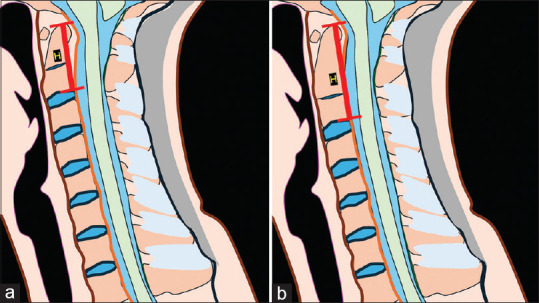

Background: Congenital block vertebrae (BV) is a common condition resulting from segmentation disorders during embryonic development, leading to the fusion of adjacent vertebrae. BV at C2-C3 (cervical vertebrae 2nd-3rd) level is the most common segmentation anomaly. Labeling this correctly is the requirement for exact labeling of the spine. Diagnosing BV may not be challenging; however, differentiating BV from the long C2 can be tricky. Our study proposes a novel method of recognizing BV by measuring their height to aid in accurately distinguishing BV from normal vertebrae.

Methods: This retrospective study compared C2 vertebral heights between two groups: 50 patients with normal cervical spine magnetic resonance imaging (MRI) and 30 patients with congenital fusion at the C2-C3 levels. Using T2-weighted midsagittal MRI images, the height of the C2 vertebra was measured from the tip of the odontoid process to the posteroinferior part of the vertebra. Data analysis was performed using independent t-tests to evaluate the differences in measurements.

Results: The mean C2 vertebral height for the normal cervical spine group was 33.22 mm, while the congenital fusion group exhibited a significantly higher mean height of 45.59 mm. These findings were statistically significant, indicating that a C2 vertebral height exceeding 33 mm is atypical in normal individuals. Our proposed threshold measurement aids in distinguishing between single vertebrae and BV.